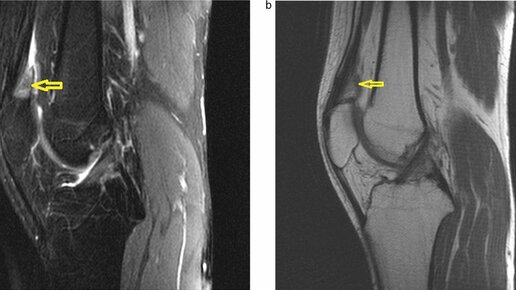

Коленный сустав – одно из наиболее крупных и анатомически сложных сочленений в человеческом теле. Он соединяет надколенник (коленную чашечку), бедренную и берцовую кости и работает наподобие шарнира. Сустав дополнительно стабилизирован внутренними и наружными связками, менисками, сухожилиями и мышцами. Одним из элементов структуры коленного сустава являются особые жировые тела (тела Гоффа), похожие на небольшие подушечки. Они расположены в области крыловидных складок (проходящих в полость сустава...

Одной из причин боли в колене принято считать болезнь Гоффа, или липоартрит (воспаление жирового тела). Я часто вижу больных после всевозможных внутрикапсульных резекций и могу сказать — каждое проникновение иглы в сустав нарушает его герметичность, сустав высыхает. Это как вместо того, чтобы накачать шину на колесе, вы вставили туда гвоздь. Жировое тело Гоффа — это помощь в амортизации коленного сустава, его передней верхней и нижней части колена. Поэтому удаление ухудшает состояние колена и ведет к артрозу, затем к замене сустава...